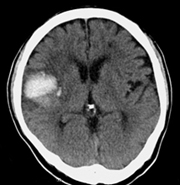

뇌혈관이 막히거나 터지는 질환을 부르는게 뇌졸중이고 그 중 뇌혈관이 막히는게 뇌경색 그리고 뇌혈관이 터지는 것을 뇌출혈이라고 합니다. 뇌졸중은 영구적인 손상이 많다고 하며 증상에 따라 전신이나 육체 일부 기능이 마비되는 등의 극심한 후유증이 남는 무서운 질병입니다 오늘은 뇌경색 초기증상에 대하여 알려드리도록 하겠습니다.

허혈성 뇌졸중은 발생 기전에 따라 대혈관 질환에 의한 뇌경색, 심인성 뇌경색 또는 심인성 뇌경색, 소혈관 질환 또는 틈새 뇌경색, 기타 드문 이유가 되는 것에 의한 뇌경색으로 나누어져요. 에피소드는 일정 기간 동안 증상이 완전히 가라앉는 경우입니다.

허혈성 뇌졸중의 대표적인 이유가 되는 것은 고혈압, 당뇨병, 고지혈증 등으로 인해서 뇌에 혈액을 전달하는 혈관에 동맥경화(동맥경화)가 발생하여 뇌로 가는 혈류를 차단하는 것입니다.